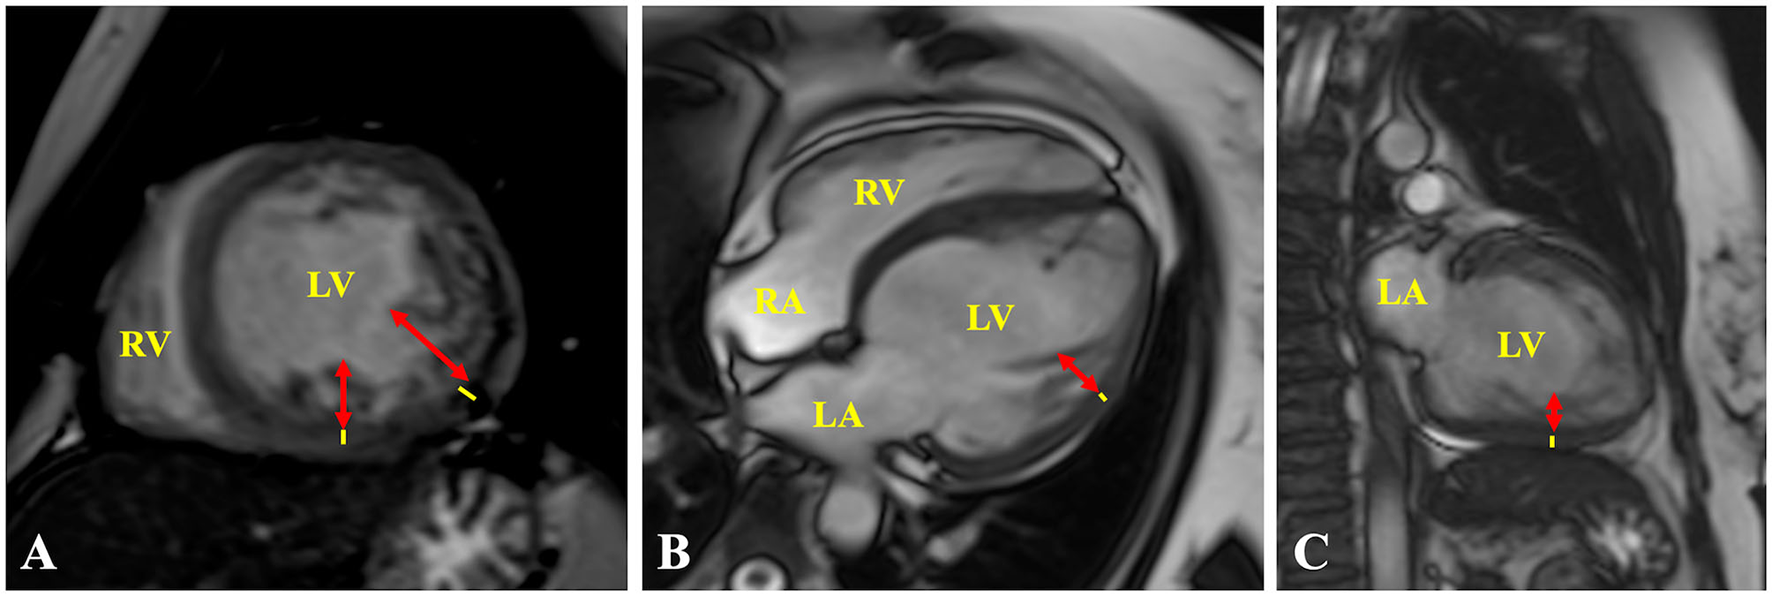

Cardiovascular magnetic resonance (CMR) imaging was performed 1 month after discharge to confirm the diagnosis and demonstrated positive diagnostic criteria for NCCM; additionally, the study did not show late gadolinium enhancement (LGE) (Figure 3). Currently, after 9 months of outpatient follow-up, the patient remains in optimal medical therapy. Bisoprolol was titrated to 5 mg bid, and dapagliflozin 10 mg OD was started. The LVEF improved slightly to ~35%, in NYHA class II, and she did not require hospitalizations for ADHF. A timeline is showcased in Figure 4.

Figure 3

Cardiac MRI. (A) Short axis, (B) 4-chamber, and (C) 2-chamber views showing representative measurements of the ratio of ticker non-compacted (redlines) to thin compacted (yellow lines) myocardium >2.3 at end-diastole, in the (A) mid-inferolateral, (B) mid-anterolateral, and (A,C) mid-inferior segments. LA, left atrium; LV, left ventricle; RA, right atrium; RV, right ventricle.

The TTE fulfills a fundamental value in the initial diagnostic approach, being Jenni's criteria the most widely used, and evaluates a two-layer ventricular myocardium with thick non-compacted and thinner compacted myocardium, generating an NC/C ratio >2 in end-systole on short-axis parasternal view (11). These alterations affect predominantly the mid-lateral, mid-inferior, mid-anterior, and apical LV areas (12). Finally, prominent excessive trabeculations and the flow between the deep intertrabecular recesses by color Doppler and excluded coexisting structural cardiac abnormalities are also considered (11). Cardiac magnetic resonance (CMR) allows us to confirm the diagnosis with 86% sensitivity and 99% specificity, following Petersen's criteria that consider an NC/C ratio >2.3 in end-diastole (11). Both criteria were met by our patient. The differential diagnosis by TTE was made with a normal variation of myocardial trabeculations, defined as less than 3 trabeculations located in the LV apex, also with LV apical thrombi, false tendons, aberrant chords, cardiac tumors, hypertrophic cardiomyopathy (HCM), and dilated cardiomyopathy (DCM) (12, 13). The LV apical thrombi are distinguished by their higher echogenicity compared to myocardium; false tendons and aberrant cords usually cross the LV cavity (13). None of these findings were observed in our patient, neither was any cardiac tumor. Recently, the characteristics of Speckle Tracking in NCCM began to be studied, evidencing a reduced global longitudinal strain, with greater involvement of the apical segments, generating a significant basal-to-apical gradient, useful to differentiate it from HCM and DCM (11, 13). Additionally, it differs from HCM, since trabeculations and crypts that can mimic NCCM are mainly limited to the basal ventricular septum or the posterior wall (13).